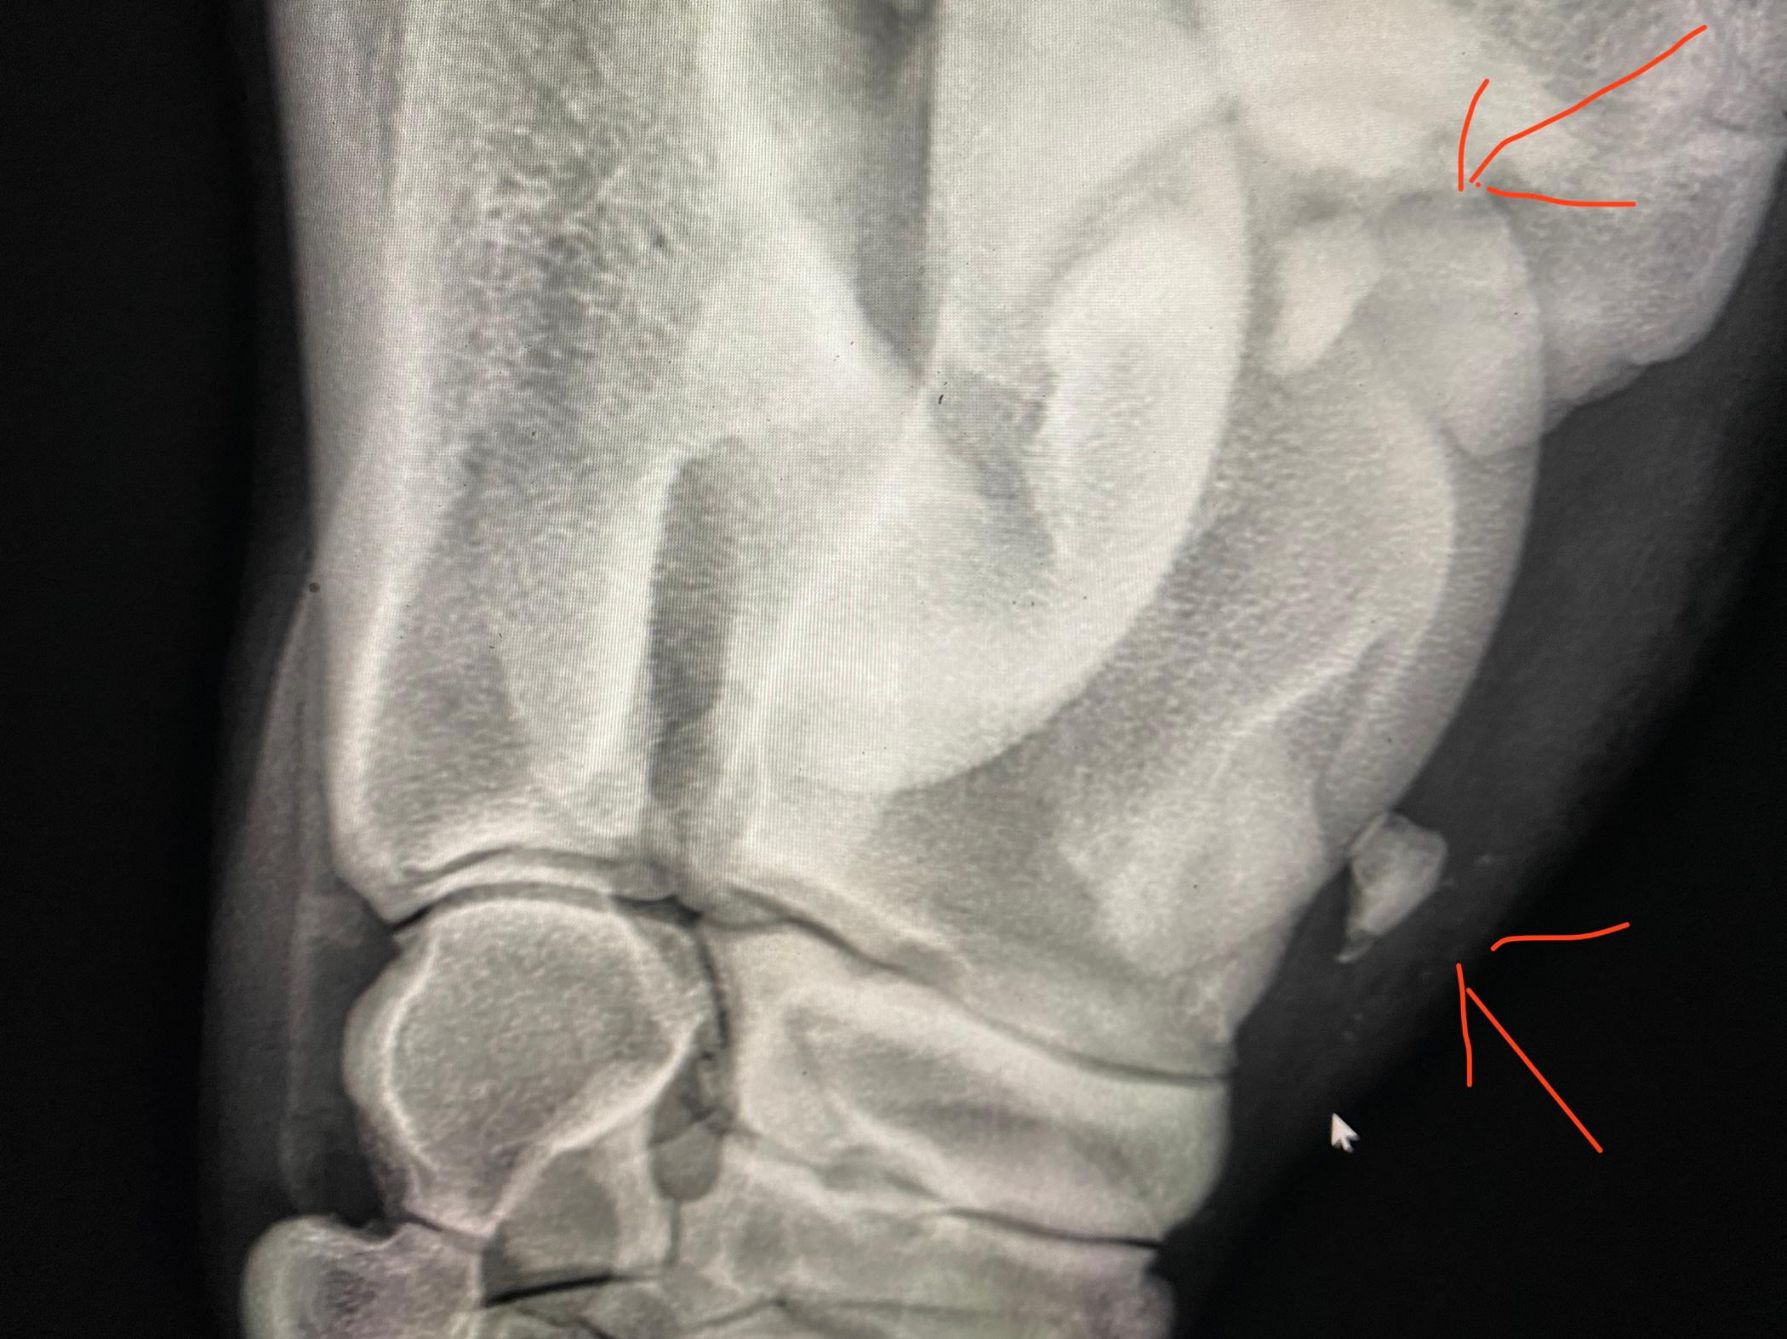

Atendemos los caballos enfermos, para lo cual se cuenta con una unidad móvil, equipada con aparato de rayos X, ecógrafo y de bioquímica sanguínea. Así mismo, realizamos las cirugías viables en el campo.